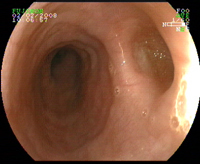

Coloscopie pour diarrhée glaireuse chez un patient ayant eu une antibiothérapie récente, qu’est ce que c’est?

Colite pseudo-membraneuse => clostridium difficile